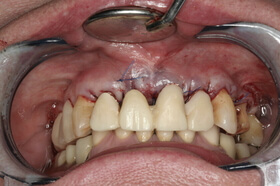

Több, mint tízéves koronák és az íny visszahúzódása a frontfogak ajak felőli oldalán

Felső négy frontfog korona cseréje és az íny visszahúzódásának korrekciója a szájpadból vett kötőszöveti lebennyel